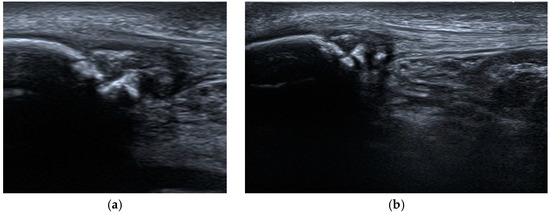

- Maruszczak, K.; Kochman, M.; Madej, T.; Gawda, P. Ultrasound Imaging in Diagnosis and Management of Lower Limb Injuries: A Comprehensive Review. Med. Sci. Monit. 2024, 30, e945413. [Google Scholar] [CrossRef] [PubMed]

- Draghi, F.; Danesino, G.M.; Coscia, D.; Precerutti, M.; Pagani, C. Overload syndromes of the knee in adolescents: Sonographic findings. J. Ultrasound 2008, 11, 151–157. [Google Scholar] [CrossRef]

- Valentino, M.; Quiligotti, C.; Ruggirello, M. Sinding-Larsen-Johansson syndrome: A case report. J. Ultrasound 2012, 15, 127–129. [Google Scholar] [CrossRef] [PubMed]